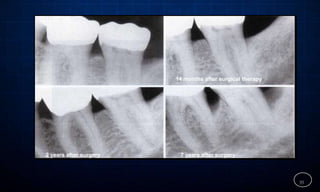

…RADIOGRAPHIC EVALUATION

 Radiographicexaminationmust beindividualized,

dependingonthe initial severityof the caseandthe

findings at the recallvisit .

 Thesearecomparedwith findingsonprevious radiographs

to checkthe boneheightandlookfor repairof osseous

defects,signsof traumafrom occlusion,periapical

pathologicchanges,andcaries.

14 months after surgical therapy

7 years after surgery

2 years after surgery